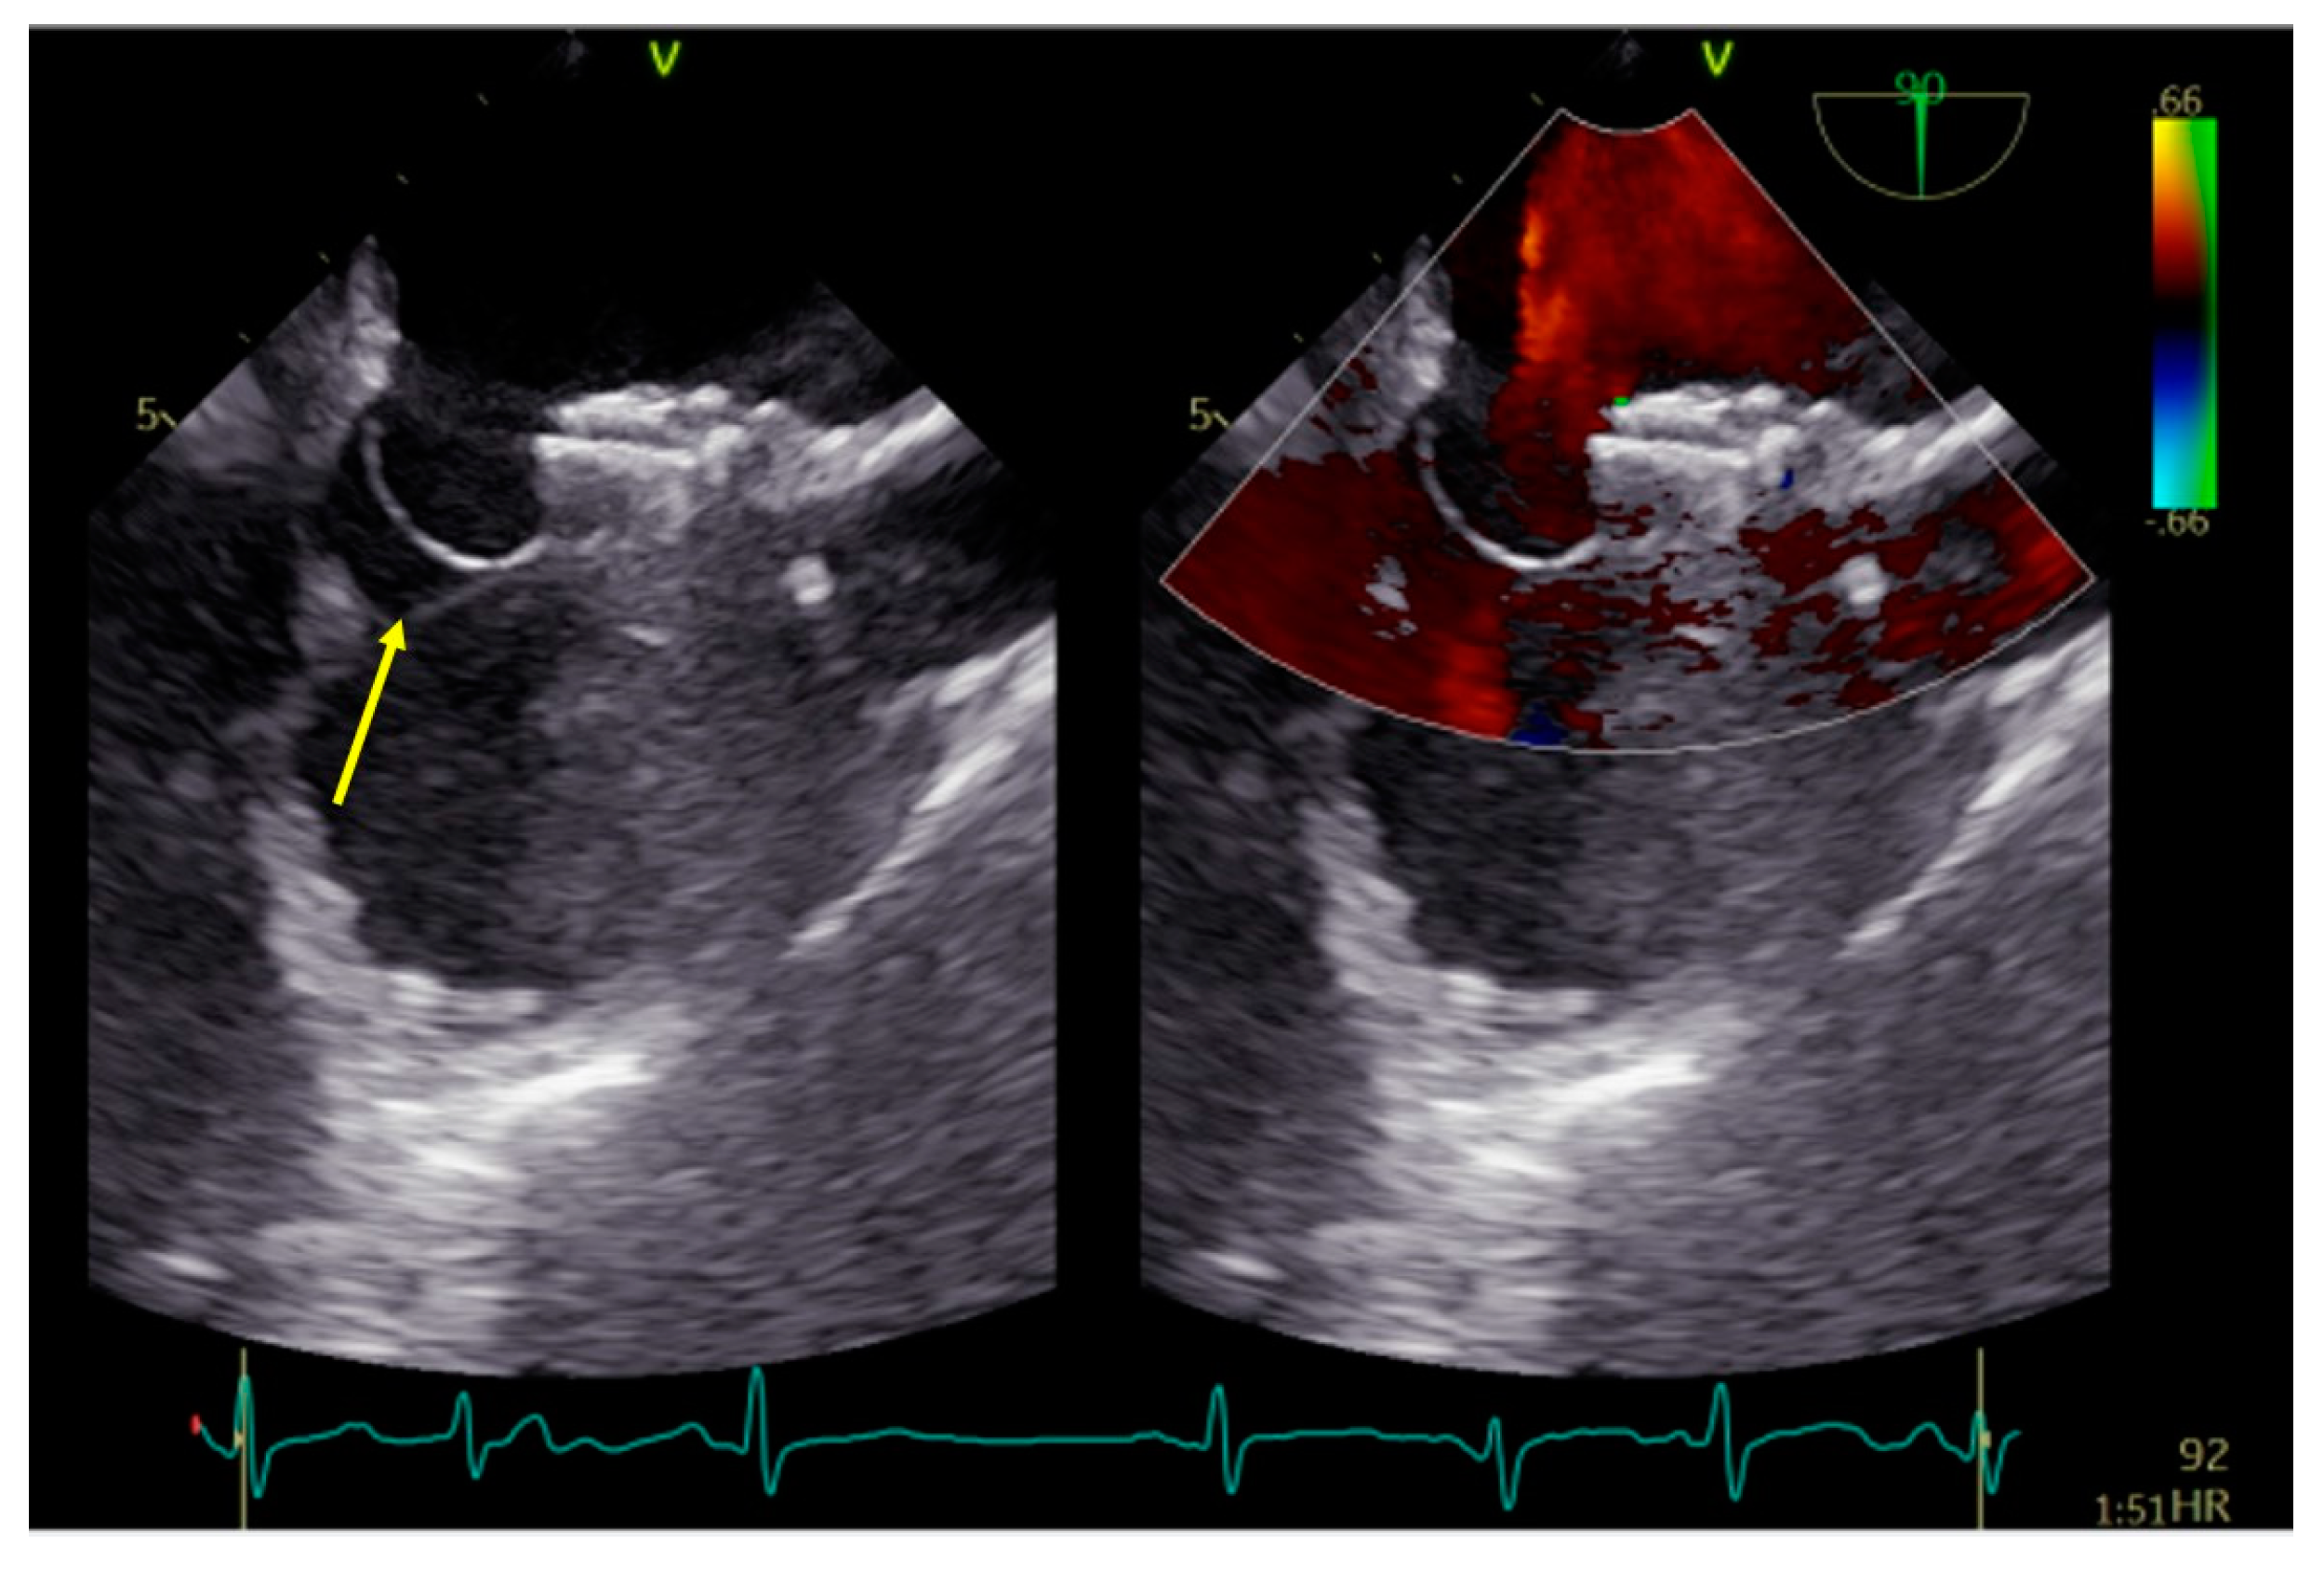

The procedure began with an ultrasound-guided puncture of the right femoral vein. A MACH 1™ Multipurpose MP1 catheter (Boston Scientific, Marlborough, MA, USA) was navigated through the PFO over the 0.035″J (Merit Medical Systems Inc., South Jordan, UT, USA) guidewire and accurately positioned in the upper left pulmonary vein. Subsequently, a 9 French (F) delivery system was placed over the Amplatz wire. Due to the aneurysmatic septum, the largest available PFO closure device, Figulla® Flex II 27/30 mm PFO Occluder (Occlutech®, Jena, Germany), was selected, and sequential deployment of the left atrial and right atrial disks was completed. However, a significant portion of the aneurysmatic and floppy IAS towards the inferior vena cava remained unstabilized (Figure 2).

Figure 2.

PFO occluder on IAS depicting a large portion of aneurysmatic and not stabilized septum (arrow). PFO−patent foramen ovale; IAS−interatrial septum.